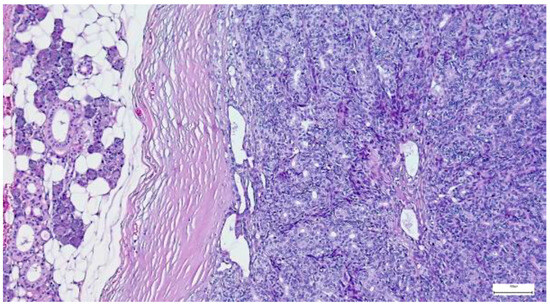

The capsule was incomplete in 67 cases (26.49%) of pleomorphic adenomas. Satellite nodules were documented as multiple nodules in 23 cases (9.09%), and as single nodules in 17 cases (6.71%). Pseudopodia were observed in 11 cases (4.34%), while both satellite nodules and pseudopodia were identified in 3 cases (1.27%) (Figure 5 and Figure 6).

Figure 5. Satellite nodule of pleomorphic adenoma in close proximity to the main encapsulated tumor (H&E staining, 5×).